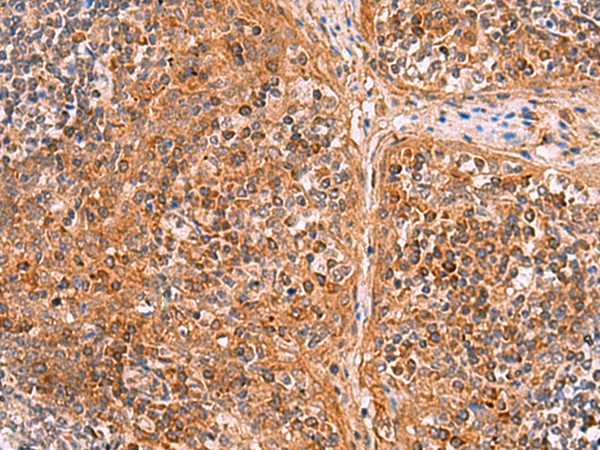

ELISA, IHC |

IHC positive control: |

Human esophagus cancer and Human tonsil |

IHC Recommend dilution: |

30-150 |